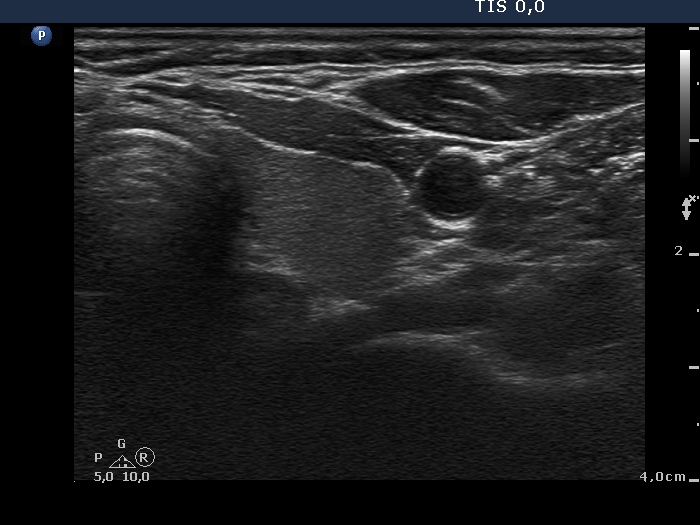

100 consecutive cases of papillary cancer - case 042 (ultrasonographic picture 5)

Left lobe, transverse scan. This lobe is intact.